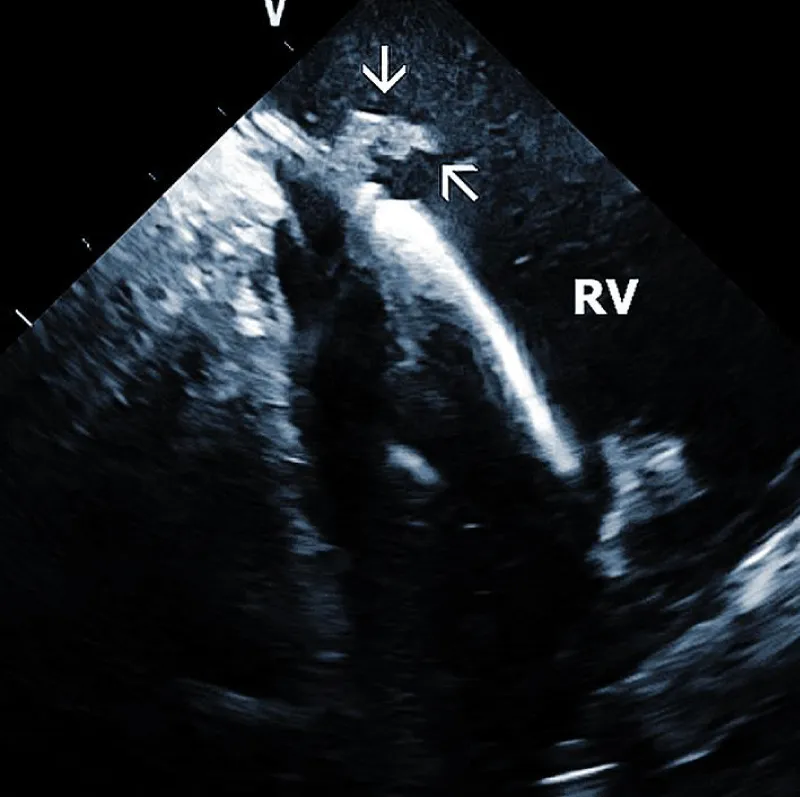

At the beginning of the procedure, ICE is introduced into the right ventricle to check and document possible pericardial effusion and left or right ventricular function. The course of the lead within the right ventricle is visible (Figure 1A). In addition, attachments of the right ventricular leads to cardiac structures could be seen, and the tip of the lead can be localized (Figure 1B).

Figure 1A: The course of two pacemaker leads (arrows) within the right ventricle (RV). The ICE catheter is positioned in the basal RV.

Figure 1B: ICD lead crossing the tricuspid valve between the right atrium (RA) and right ventricle (RV). Arrows mark lead adherent echodensities. The ICE catheter is positioned in the RA.